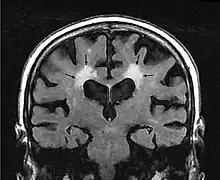

MRI image: Leukoaraiosis in a 90-year-old patient with cerebral atrophy.

Leukoaraiosis is a particular abnormal change in appearance of white matter near the lateral ventricles. It is often seen in aged individuals, but sometimes in young adults.[1][2] On MRI, leukoaraiosis changes appear as white matter hyperintensities (WMHs) in T2 FLAIR images.[3][4] On CT scans, leukoaraiosis appears as hypodense periventricular white-matter lesions.[5]

These white matter changes are also commonly referred to as periventricular white matter disease, or white matter hyperintensities (WMH), due to their bright white appearance on T2 MRI scans. Many patients can have leukoaraiosis without any associated clinical abnormality. However, underlying vascular mechanisms are suspected to be the cause of the imaging findings. Hypertension, smoking, diabetes,[3] hyperhomocysteinemia, and heart diseases are all risk factors for leukoaraiosis.